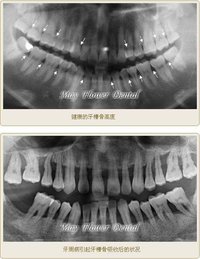

骨吸收的程度一般按吸收區占牙根長度的比例來描述,通常分為三度.

Ⅰ度:牙槽骨吸收在牙根的頸1/3以內.

Ⅱ度:牙槽骨吸收超過根長1/3,但在根長2/3以內,或吸收大根長的1/2.

Ⅲ度:牙槽骨吸收占根長2/3以上.

牙槽骨吸收的方式和程度,可通過X線片來觀察。正常情況下,牙槽嵴頂到釉牙骨質界的距離約為1~2mm,若超過2mm則可視為牙槽骨吸收。牙周炎的骨吸收最初表現為牙槽嵴頂的硬古板消失,或嵴頂模糊呈蟲蝕狀。